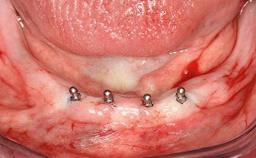

An 83-year-old man presented together with his caregiver at the dental department of the Medical University of Innsbruck, Austria with complaints of swelling in the right maxillary canine area and loss of retention of his 5-years-old mandibular denture. The patient had a significant medical history (20 years) of bipolar affective disorder with moderate depression (F 31.3) and dementia in Alzheimer’s disease (F 00.2). The patient had been in ambulant psychiatric therapy for his depressive illness for the past 20 years. He lived alone and had no children; his sister assisted with daily living. She reported that the patient exhibited compulsive hoarding behavior. In the previous two months, she had noted increasing disorientation and vertigo in the patient. She therefore accompanied him for a medical consultation at the Department of Psychiatry and Psychotherapy of the Medical University of Innsbruck. He was released home after a 6-week inpatient stay.

# of Implants 2

Defining Characteristics Fully edentulous lower jaw to be rehabilitated with two or more implants

Modality 2 interforaminal implants